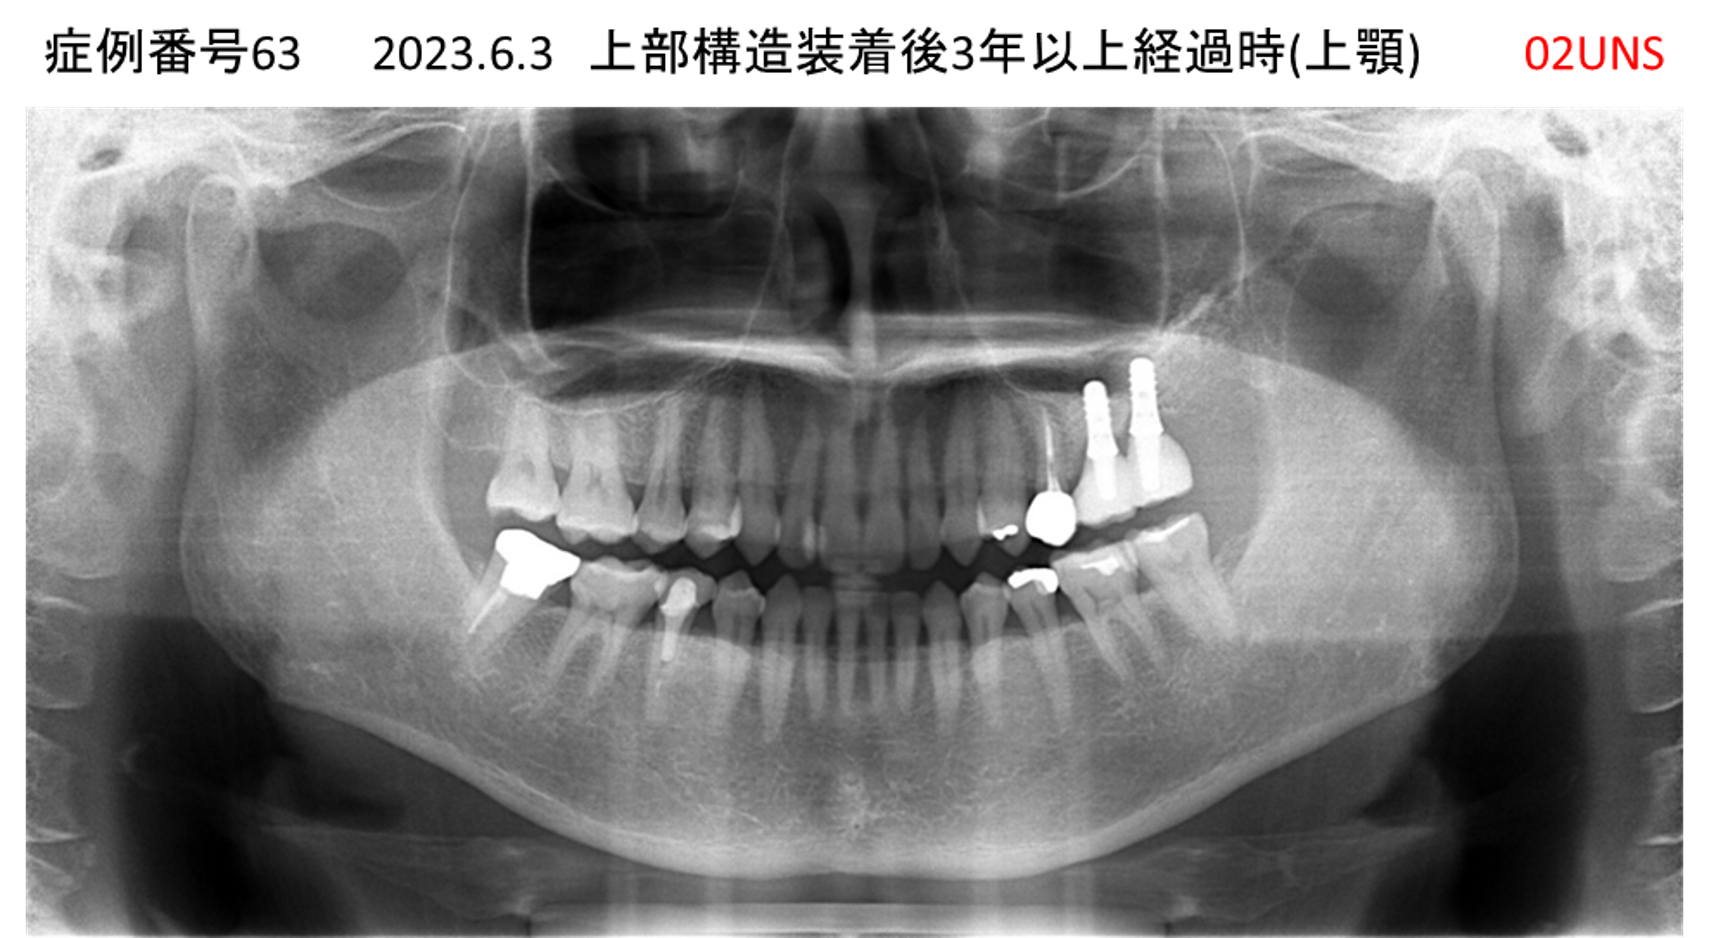

上の前歯が揺れていて痛い患者様のインプラント症例

| 治療名称 |

インプラント |

| 治療費用 |

295万円+税 |

| 治療期間 |

6か月 |

| 患者さんの症状(主訴) |

上の前歯が揺れていて痛い |

| 治療内容 |

抜歯即時インプラント |

| 治療結果 |

痛みがなく、しっかり噛める。 見栄えがとても良い |

| 治療の注意点(リスク/副作用) |

インプラントが壊れたら再治療が必要 |